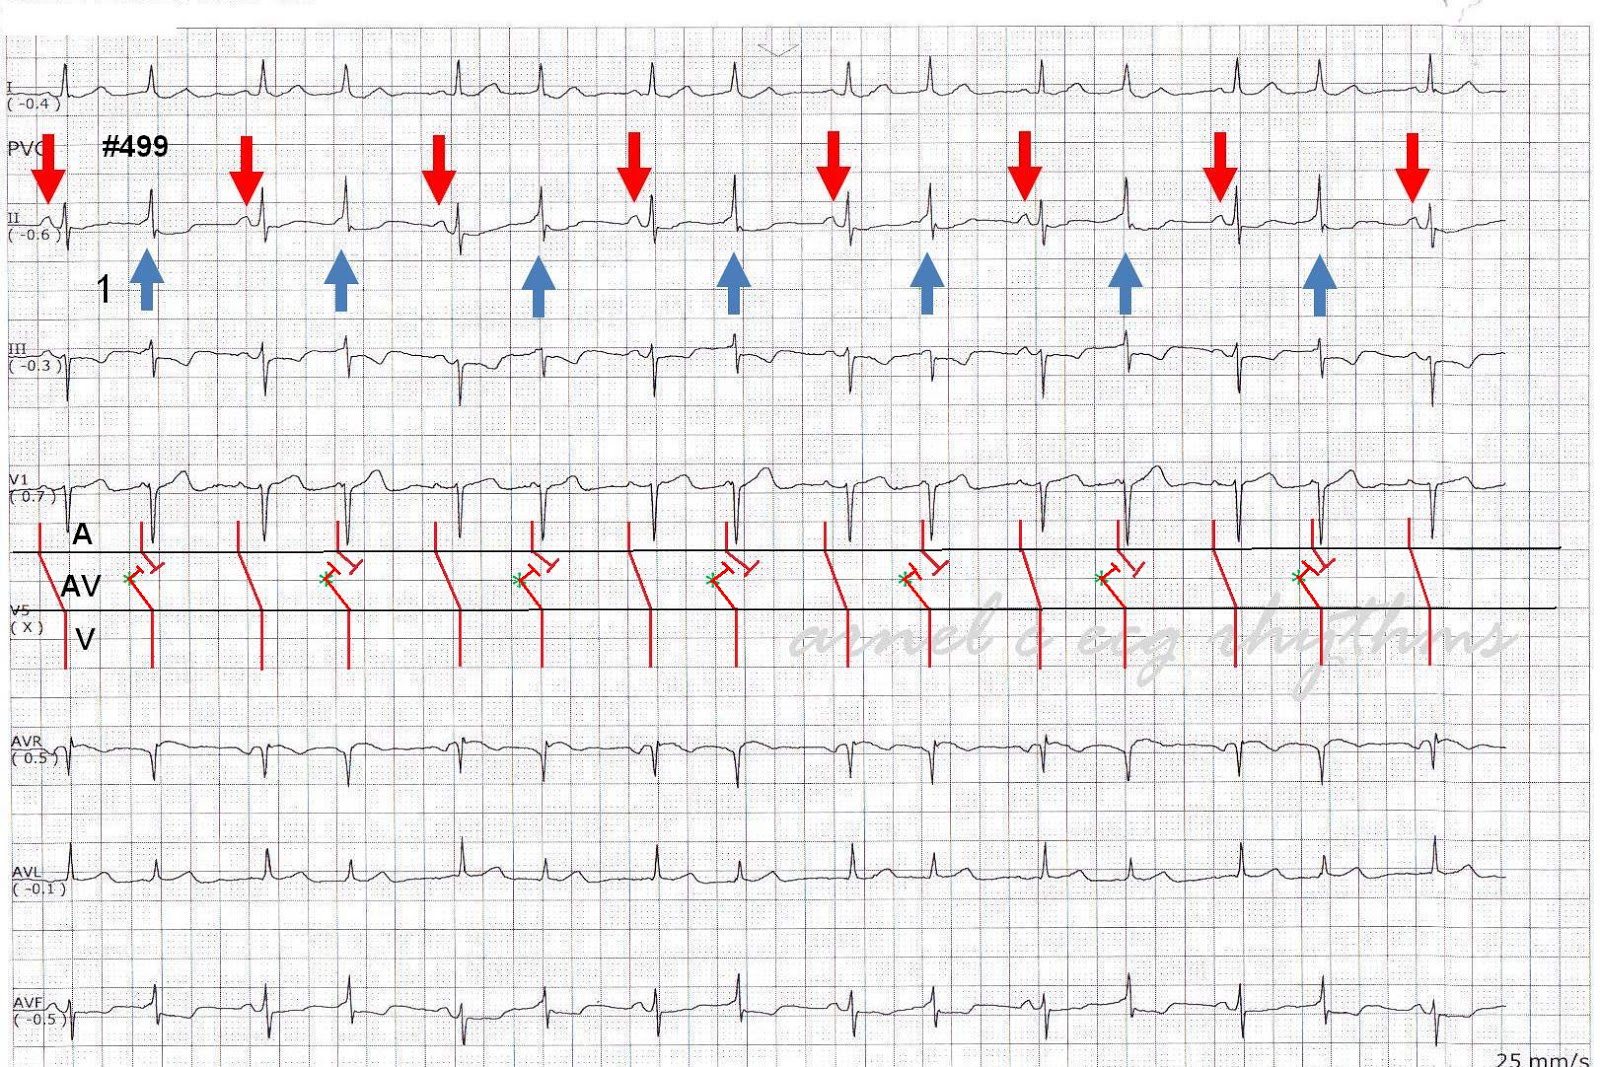

ECG Channel AV dissociation What Is Av Dissociation In Ecg Atrioventricular (av) dissociation is a condition in which the atria and ventricles do not activate in a synchronous fashion but beat. Impulse conduction from the atria to the ventricles may be abnormally delayed or even blocked. We see the classic “av dissociation” of complete heart block. The ecg demonstrates complete av dissociation, with independent atrial and ventricular rates. It can. What Is Av Dissociation In Ecg.